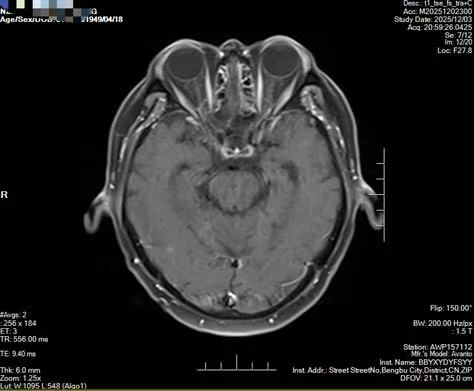

放疗后患者脑部磁共振

今年12月复查脑部MRI时,结果显示:脑转移肿瘤已完全消失。